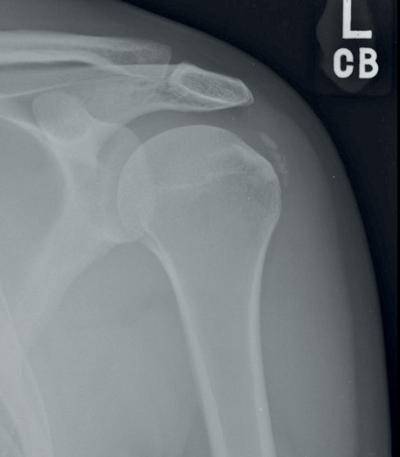

Figure 2: X-ray of author’s left shoulder, demonstrating calcific

deposits in the region of the supraspinatus tendon.

I explained the problem to my boss, before bleeping the on-call orthopaedic SpR and ending up in A&E for an x-ray. The A&E consultant examined me, before grimly informing me that, “The x-ray is unequivocal (Figure 2), you have calcific tendonitis of your supraspinatus. It can take weeks to months to improve, and after that you may be left with reduced function. You’ll need rest, physiotherapy, possibly a steroid injection and sometimes even an arthroscopy.”